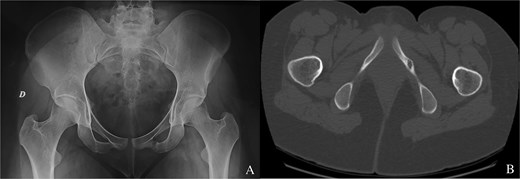

The patient received acetylsalicylic acid, with partial clinical improvement. The decision was made to perform a surgical drilling and curettage of the tumour with the help of a customized 3D-printed guide (Fig. 2A–C). The patient underwent surgery on a standard table, in supine position, under general anaesthesia. A mini-Pfannenstiel approach (on the pubic symphysis) was performed to expose the proximal and medial border of the left iliopubic ramus, which served as a fixed landmark for positioning the guide (Fig. 3A). Once the guide had been pinned in place, a K-wire was inserted in the direction of the tumour. A fluoroscopic check verified the K-wire positioning (Fig. 3B). A soft tissue protection instrument was used to guide the cannulated drill bit towards the tumour (Fig. 3C). Drilling and curettage of the lesion was performed under fluoroscopic control with anteroposterior, inlet, and outlet views of the pelvis (Fig. 3D and E). The anatomopathological examination confirmed the diagnosis of osteoid osteoma, which was completely resected. Pain disappeared in the immediate postoperative period. At 24-month follow-up, we did not note recurrence of the tumour (Fig. 4A and B). Written informed consent was obtained from the patient.

(A) Two customized 3D-printed drill guides for more precision. (B) A customized 3D-printed drill guide with two K-wires positioned in the direction of the tumour. (C) A customized 3D-printed drill guide with one K-wire positioned in the direction of the tumour.